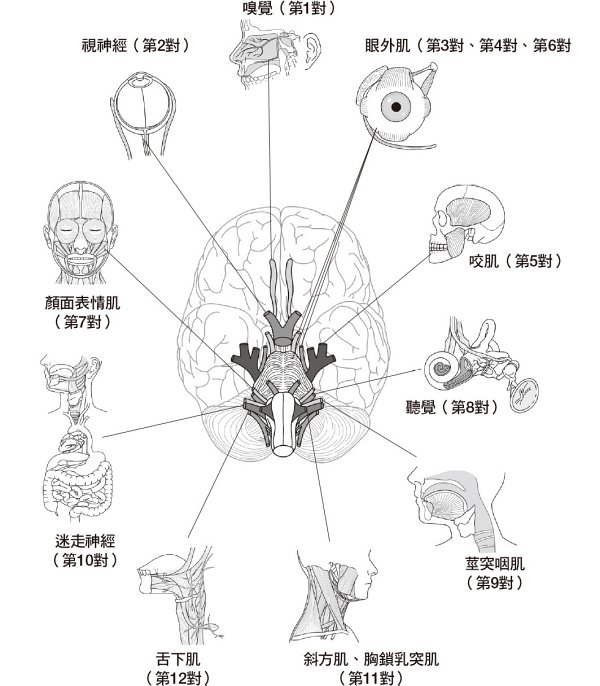

【圖1-1】生存在現代社會的原始人大腦。 內側前額葉皮質(mPFC)和杏仁核(Amygdala)緊密相連並互相牽制,當一方發揮功能時,另一方的功能就會降低。就像蹺蹺板一樣,以一個上升、另一個就下降的方式運作。